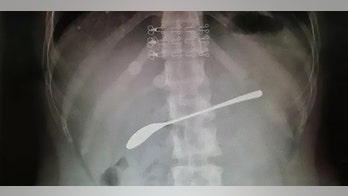

Surgery September 10, 2019 Drunk woman swallowed 6-inch spoon and forgot, report says Fan said that if his patient had waited, or ignored the pain, the spoon could’ve caused ulcers or life-threatening infection.